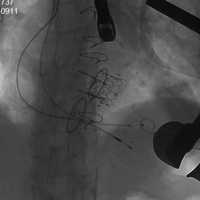

病例四(经颈静脉三尖瓣瓣中瓣)

患者女性,69岁,既往行三尖瓣生物瓣置换术,置入HANCOCK II 29#瓣膜一枚。STS评分11.75%,属于外科换瓣手术高风险患者。术前心脏超声示原三尖瓣生物瓣衰败,瓣叶脱垂,三尖瓣轻度狭窄并中量反流。术前详尽评估,经股静脉路入同轴性不理想,故术中选择经右颈静脉途径植入27# Renato球扩式瓣中瓣,释放成功后瓣膜功能良好,无明显瓣中及瓣周反流,平均跨瓣压差2.8mmHg。

瓣膜释放 术后右室造影